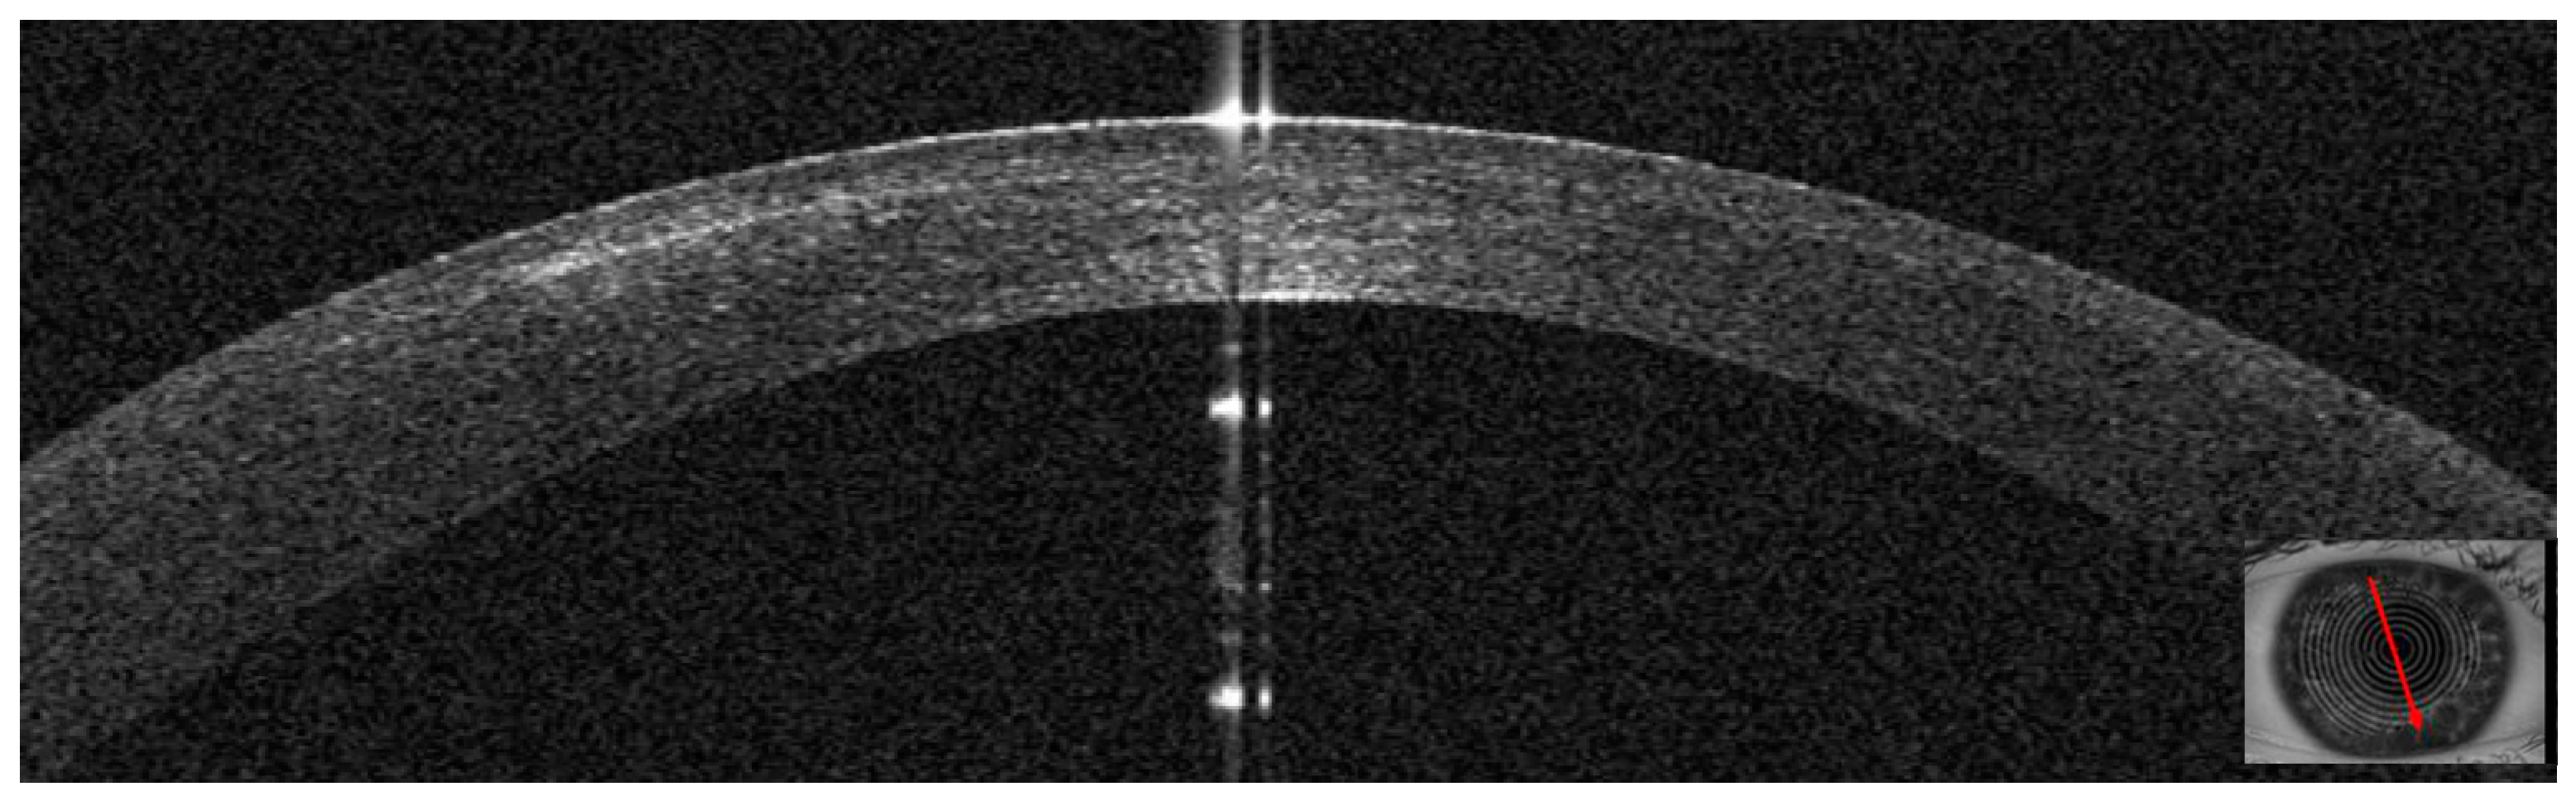

3.4. Patient #4